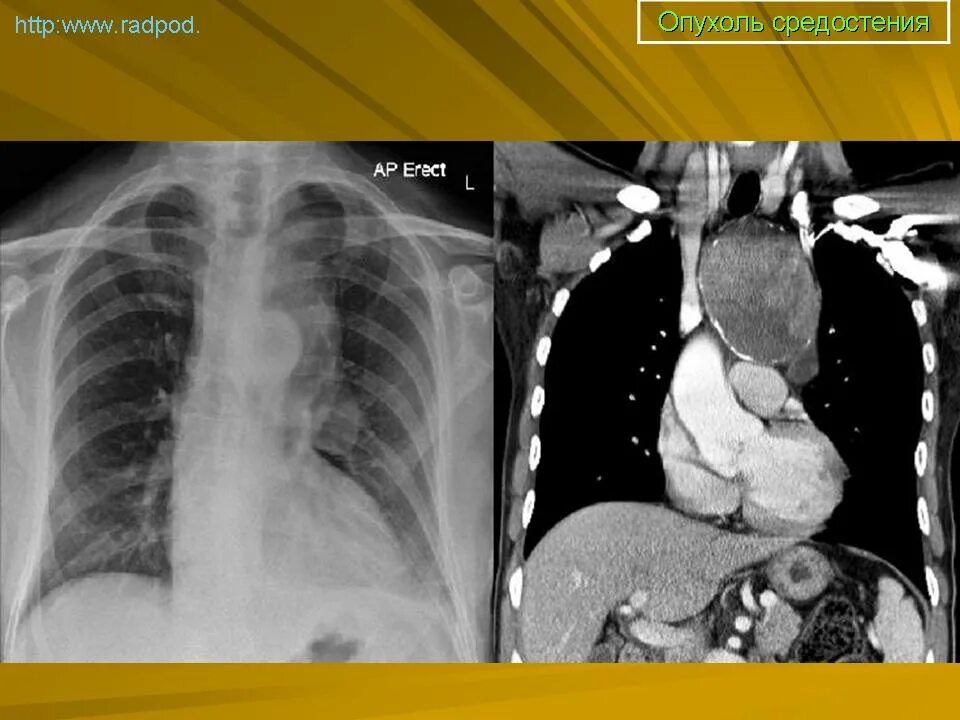

Лечение опухолей средостения